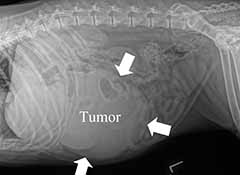

Based on abdominal x-rays or abdominal ultrasound, your pet’s veterinarian may make a presumptive diagnosis of a liver tumor. (Figure 1) Due to the complexity of liver surgery and the risk of bleeding complications during surgery, many primary care veterinarians will refer your pet to an ACVS board-certified veterinary surgeon for removal and post-operative care.